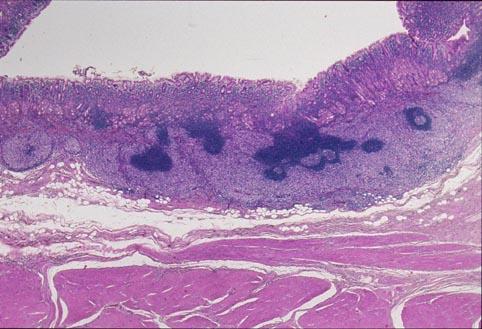

疾病(病理主体)的分类恶性淋巴系统・血液系统肿瘤/ATL (成人,ATL细胞白血病)

检查方法病理切片(微观)

肿瘤的肉眼分类0型(表在型)/IIa型(IIa+IIc)

肿瘤最大直径20~24

肿瘤的深度sm

多发性肿瘤(同一器官)有(同时性)

多重性肿瘤(多个器官)有(同时性)